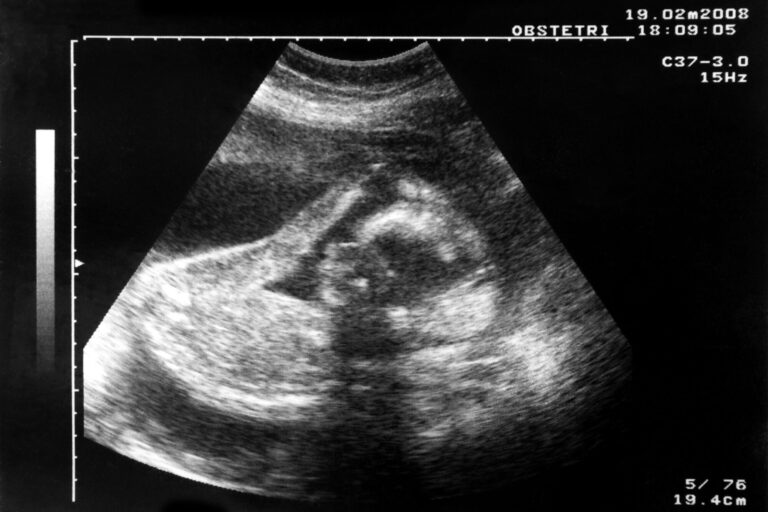

The fetus’s health is what worries pregnant women the most. Associate Professor Bente Prytz Mjølstad explains that especially first-time mothers tend to overuse prenatal checkups compared to what is recommended in the basic healthcare program. Illustrative photo: Colorbox